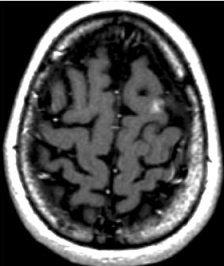

Day of Radiosurgery

Picture of brain Metastatsis Day of Radiosurgery

MRI scans of a brain metastasis from breast cancer shown on the day of radiosurgery, 5 months later, and 3 years later